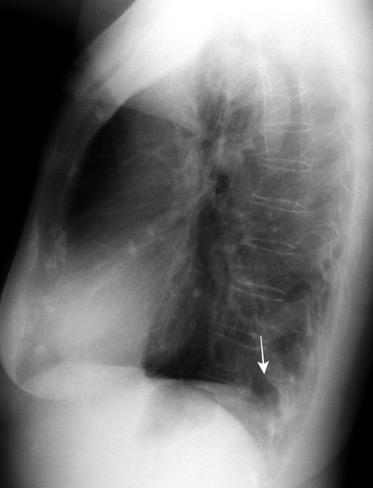

Paciente que ingresa con síntomas de colecistitis aguda. Antecedentes de trauma importante muchos años antes

Zhao L et al. Delayed traumatic diaphragmatic rupture: diagnosis and surgical treatment. © Journal of Thoracic Disease.

J Thorac Dis 2021

Asas

Líquido pericolecistítico

V. biliar con cálculos

Diafragma